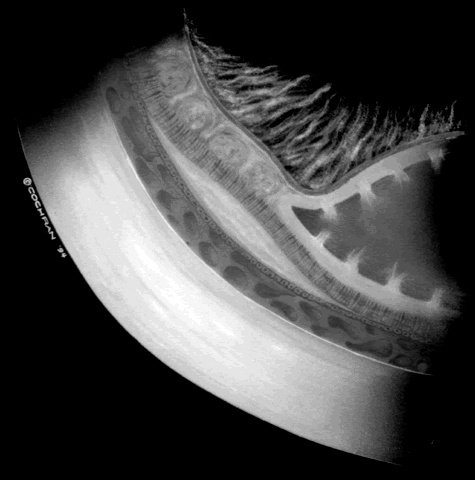

The suggested treatment is scleral buckling or vitreous surgery, including removal of the inner wall of the schisis cavity with extensive panretinal photocoagulation to protect against rhegmatogenous retinal detachment.36–38 The hallmark of this tractional detachment is visual field changes that are larger than expected relative to the schisis cavity.36 Previously, demarcation lines resulting from full-thickness retinal detachment have been reported posterior to the schisis cavity.39 Others have considered this finding to represent an undetected rhegmatogenous retinal detachment, but based on observations during surgery, we believe that this detachment can be reversible and is tractional in origin (Fig. 6).36